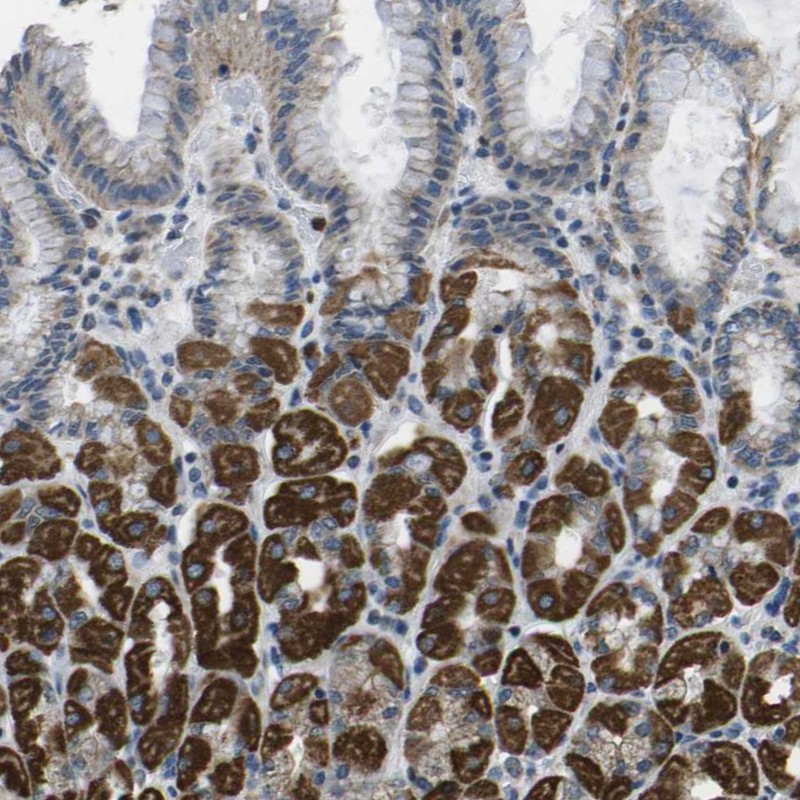

Immunohistochemical staining of human stomach shows strong positivity in Parietal cells.